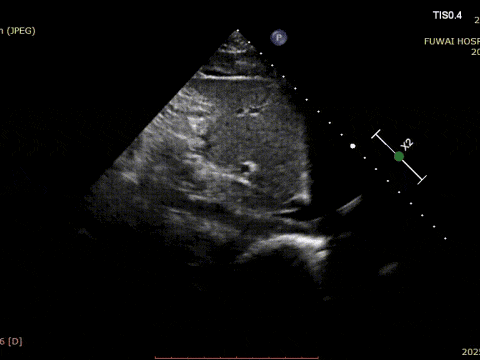

At Fuwai Hospital Shenzhen, Dr. Lu Yaoxing's team recently performed a successful transcatheter closure of a secundum atrial septal defect (ASD) using a MemoSorb biodegradable occluder in a 34-year-old male patient with a rare coronary anomaly.

1. L'ASD était situé au centre, avec un diamètre mesuré d'environ 8,1mm (vue bicavale) et de 8,2mm (vue aortique sur axe court).

2. CTA coronaire a révélé une origine anormale de l'artère circonflexe gauche (LCX) du sinus coronaire droit, avec un cours entre l'aorte et l'oreillette gauche.

3. La distance entre l'ASD et la LCX aberrante n'était que d'environ 6mm.

4. il n'y avait pas de jante aortique, et les jantes inférieures et postérieures étaient relativement molles.